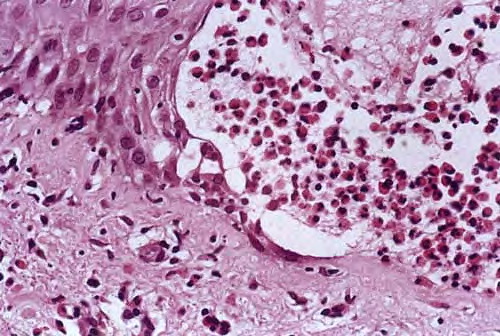

In early lesions, papillary dermal edema in combination with a cell-poor or cell-rich perivascular lymphocytic and eosinophilic infiltrate is present. The blister arises at the dermal-epidermal junction . In the cell-rich pattern, which correlates clinically with blisters arising on erythematous skin , eosinophilic papillary abscesses may develop with numerous perivascular and interstitial eosinophils intermingled with lymphocytes and neutrophils in the superficial and deep dermis. Early lesions may have the histologic features of eosinophilic cellulitis (Well’s syndrome). Eosinophilic spongiosis may occur. The cell-poor pattem is observed

when blisters develop on relatively normal skin , in which there is usually a scant perivascular lymphocytic infiltrate with few eosinophils, some scattered throughout the dermis and others near the epidermis. The blister contains few inflammatory cells. Epithelial migration and regeneration may result in an intraepidermal split in older blisters. Similar to pemphigus vegetans, a hyperplasia of the epidermis, subepidermal bullae, and accumulations of eosinophils and lymphocytes may be seen.